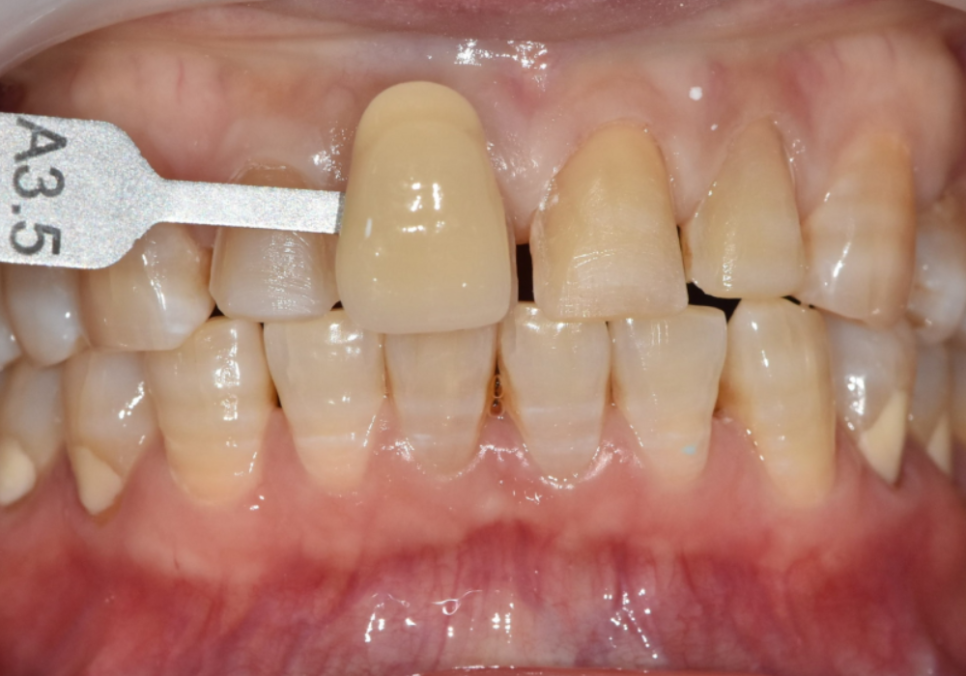

색상은 환자분이 원하시는 밝기 범위 안에서,

자연스럽고 건강해 보이도록 제작했습니다.

250228